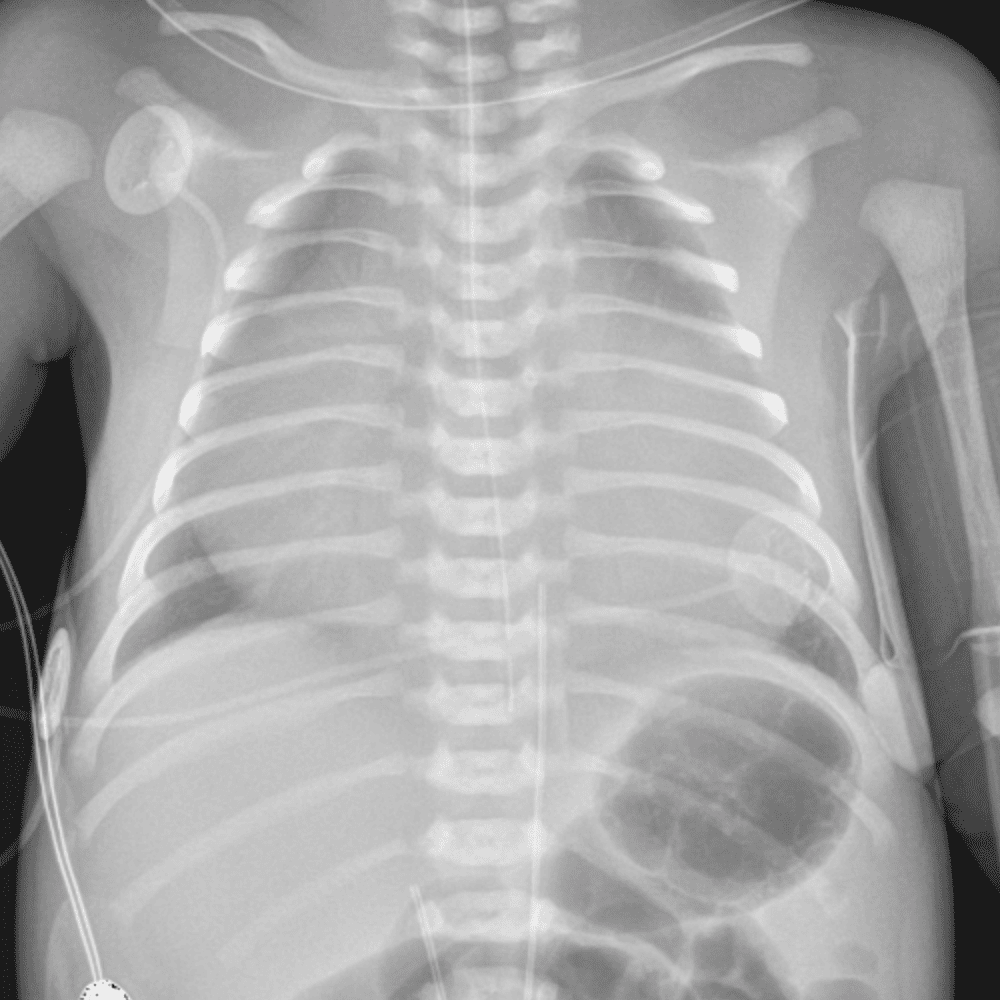

Peds Chest

Practice

Simulates call by including subtle or difficult cases and some normals.

50 cases